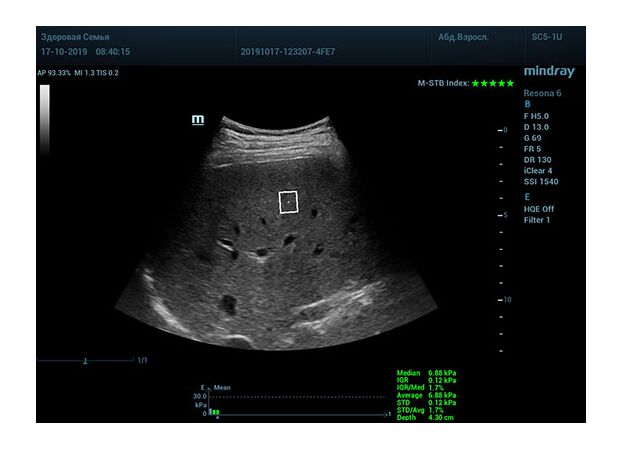

Определение плотности печени. Не ошибся ли оператор при измерении эластических свойств печени? Для оценки критериев качества предусмотрен индекс MBT, который покажет насколько «твердой» была рука оператора и двигалась ли печень. При MBT 5* рука тверда и показатели достоверны. Для оценки качества результатов используется IQR индекс, отображающий колебания показателей в точке измерения при расчете медианы. Показатели при IQR <30% считаются приемлемыми. Техника сканирования через межреберные промежутки требует размещение окна интереса на несколько сантиметром ниже капсулы, для исключения эффекта реверберации. Установка ROI на паренхиму без захвата сосудов, для исключения погрешностей измерения.

Стадия фиброза определяется по системе METAVIR Staging, построенной на данных биопсии и сопоставлении с данными эластографии. Своевременная диагностика фиброза, и начало его лечения, залог благоприятного исхода заболевания.

• METAVIRF0 – норма.